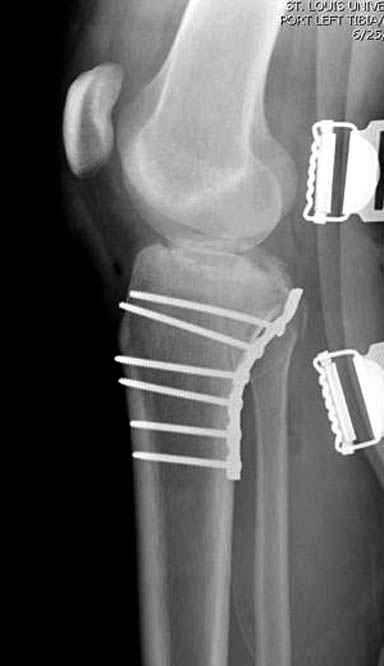

При сложных переломах тибиал плато для своего рода Damage Control мы иногда применяем поэтапную тактику. Сперва оперируется одна сторона, а потом после рекондиции мягких тканей окончательный этап.

Если состояние мягких тканей позволяет, я бы предложил такой метод для вашего больного. Без предварительного планирования будет трудно, но шанс не надо упускать. Всего несколько дней после операции, и такая тактика лучше, чем недовольный молодой пациент.

Доступ к медиальной стороне задний или медиальный, через pes или в пространстве между medial gastroc мышцы.

Надеюсь, представленные снимки разных случаев помогут разобраться в тактике, и критика примется без личной обиды.